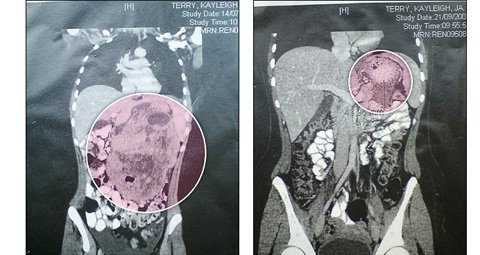

Sau nhiều cơn đau âm ỉ ở vùng bụng và dấu hiệu mệt mỏi thường xuyên, Kayleigh Terry đã đi chụp siêu âm. Ảnh chụp đã cho thấy một hình ảnh đáng sợ: Terry đang mong trung bụng một khối u to bằng quả dưa hấu, chèn từ khu vực dưới ngực xuống bụng dưới.

Sau giai đoạn xạ trị, kích cỡ khối u đã được thu nhỏ từ quả dưa hấu xuống bằng quả chanh. |

Sau hai tháng xạ trị, khối u đã được thu nhỏ xuống còn bằng cỡ quả chanh.